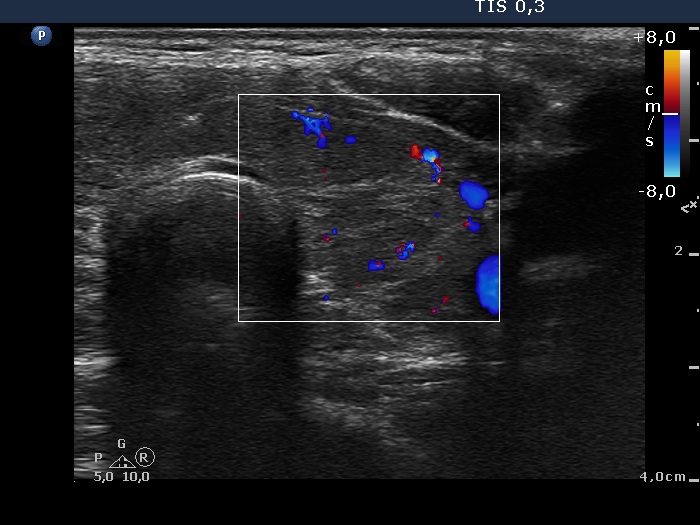

Left lobe, transverse scan, color Doppler mode. The vascularization is not specific.